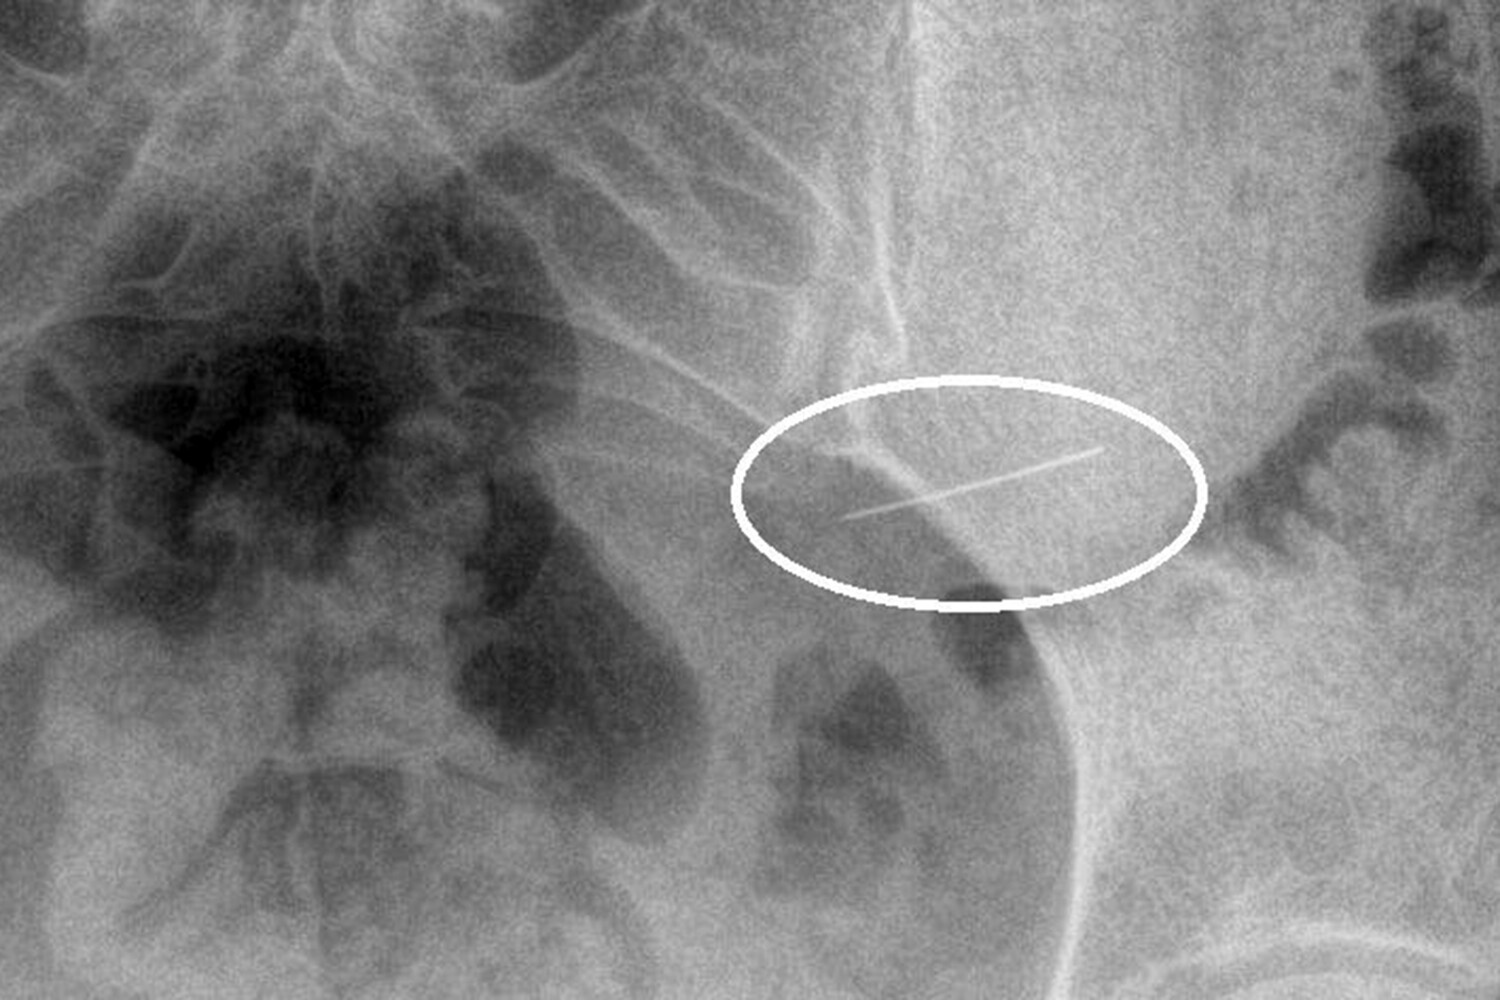

Пациентка вовремя обратилась за помощью, и бригада скорой доставила ее в стационар. Рентген брюшной полости показал инородное тело в желудке. Врачи первого хирургического отделения подготовили ее к экстренной операции, после чего с помощью современного оборудования эндоскописты аккуратно удалили опасный предмет, не допустив осложнений.